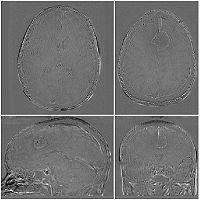

Checkerboard

Builds a "puzzle-piece" collage of blocks from both images, alternating between the two. Helpful if the two images are from different modality or have different contrast. Continuity of edges becomes very apparent on such images.

Case10-FLIRT-axial.jpg

Case10-FLIRT-saggital.jpg

Case10-FLIRT-coronal.jpg